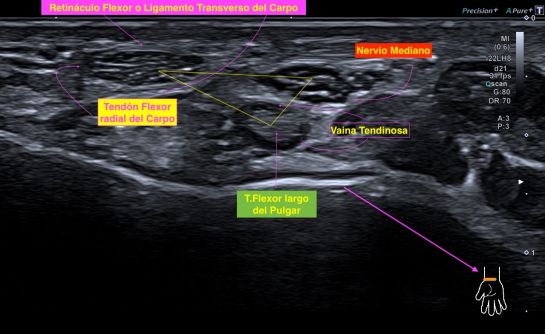

309. Afectación del Nervio Mediano

Paciente que acude por corte en la región anterior y central de la muñeca.

Después de 20 días nota parestesias en los dedos. La herida está cicatrizada, pero el movimiento es limitado.

Voy a tratar de explicarte en 4 imágenes los hallazgos para que veas la complejidad del caso, de la anatomía y de la exploración ecográfica de la cara anterior del la muñeca.

Primero necesitamos conocer bien la anatomía de esa región. En la parte central de la muñeca el nervio mediano ya se ha situado por encima de los tendones flexores de la muñeca que luego se convertirán en en los músculos flexores de la cara anterior del antebrazo, previamente en nervio mediano, más en la muñeca, a distal, es mas profundo y radial.

En el lugar del corte el nervio mediano es muy superficial antes de hacerse más profundo entre la musculatura flexora superficial y profunda del antebrazo anterior. Ahí donde más expuesto está es donde se produce el corte que estudiado en eje largo nos ofrece esta imagen preciosa, mira:

En la imagen aprecias claramente como la superficie de la muñeca está afectada por un tejido cicatricial, fibroso, heterogéneo, típico de una herida de reciente curación.

Más profundo el nervio mediano, comprimido por la fibrosis y claramente afectado en esta localización en su parte más superficial. Así mismo y fruto de la presión ejercida en capas, el flexor, más pequeño y cóncavo bajo el tejido neuronal afectado. Claramente afectación de las dos primeras capas.

Explicarte estos cambios individualizadamente es complicado a sí que voy a usar la comparativa de normalidad y patología de amabas muñecas y vas a poder ver como cambia el aspecto, las medidas tanto en milímetros como en áreas.

Observa las medidas, observa en esta imagen superior el Retináculo afectado, engrosado, hiperecogénico.

Como en las últimas 3 imágenes comparativas puedes ver perfectamente la afectación local, pero en esta imagen final que tienes arriba justo, ves la afectación global de todas la ecoestrusturas que componen la anatomía locorregional.

El proceso cicatrizador afectando al nervio y a las partes blandas es evidente, muy plástico, uno de lo estudios más bonitos que he hecho, con la calidad de la imagen de CANON MEDICAL.